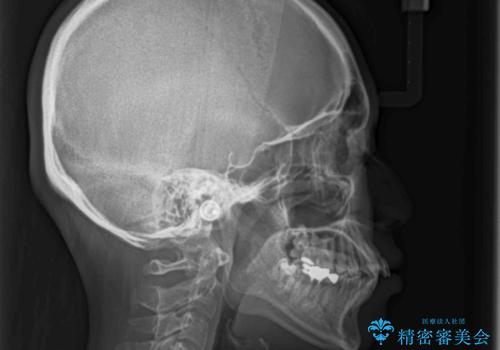

- 口の閉じにくさと割れてしまった奥歯を気にして来院された患者様です。

IPR(歯と歯の間を削る)と歯列全体の後方移動によって口元が引っ込むように設計し、インビザラインにより治療を行うこととしました。

上下正中がずれていたため、抜歯による矯正治療も検討しましたが、口元がそれほど突出していなかったため、非抜歯にて矯正することになりました。

その結果正中のズレは残りましたが、口を閉じたときの感覚や奥歯の咬み合わせには全く問題なく、患者様には大変満足していただきました。